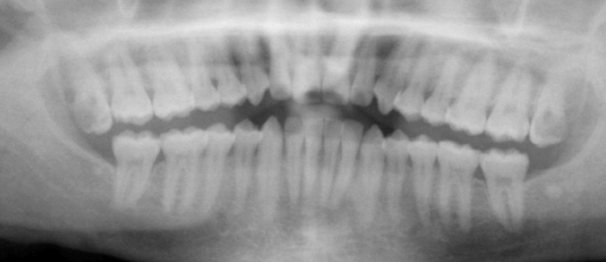

what type

HBL